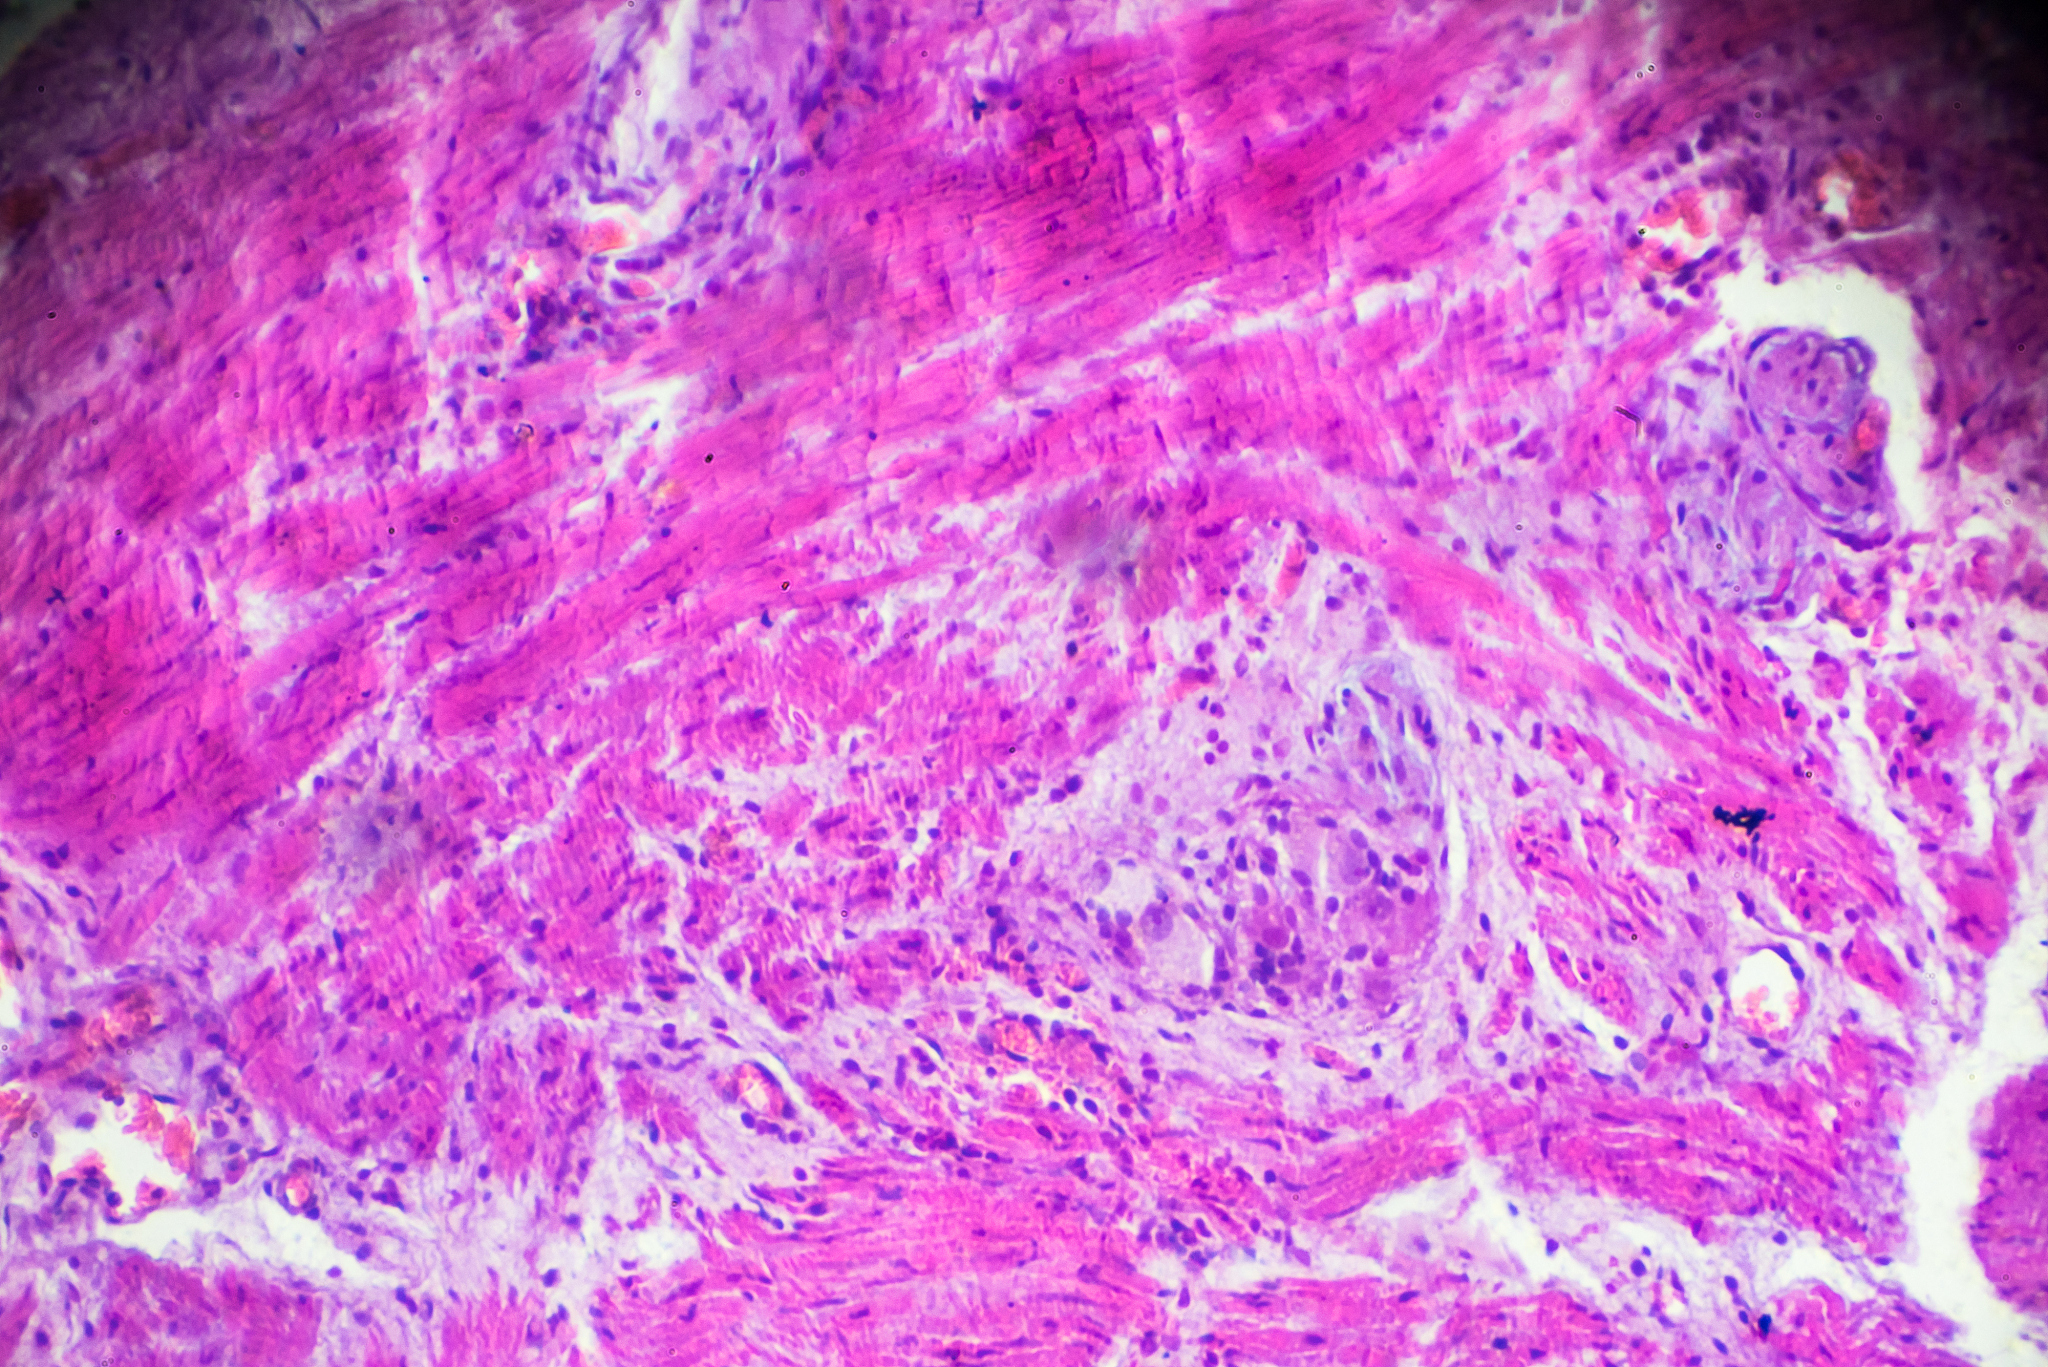

WORLD JOURNAL OF SURGICAL ONCOLOGY涵盖了外科肿瘤学的各个方面,包括原发性和继发性肿瘤的诊断、治疗和预后评估等。该期刊发表的文章涵盖了各种类型的肿瘤,包括但不限于乳腺癌、结直肠癌、胃癌、肺癌、肝癌、胰腺癌、骨肉瘤等。

WORLD JOURNAL OF SURGICAL ONCOLOGY的目标读者包括外科医生、肿瘤学家、病理学家、放射治疗师和其他相关领域的专业人士。该期刊的目标是成为外科肿瘤学领域的重要信息来源,为研究人员和临床医生提供最新的科学进展和临床实践指南。